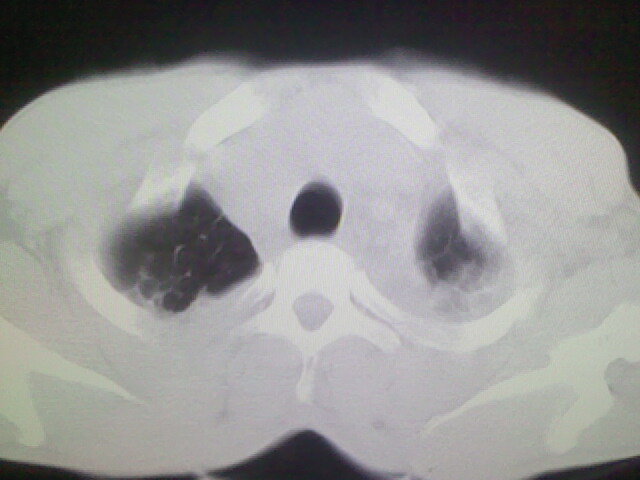

以下是引用杀毒软件在2008-9-3 6:11:00的发言:[br]侵袭性胸腺瘤------一般不侵到气管旁[br][br]考虑----纵隔淋巴瘤,心包及胸膜受累

以下是引用随光逐影在2008-9-3 7:07:00的发言:[br]1)考虑淋巴瘤可能。2)双侧胸腔积液(以左侧为甚)。3)心包积液。